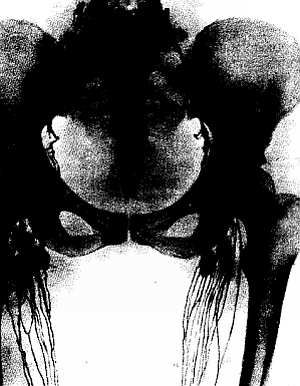

Рис. 262.Нормальные лимфатические сосуды и узлы области бедра и таза живого человека. Рентгенолимфография.

Рентгенолимфография была впервые разработана в Советском Союзе. А. С. Золотухиным и М. Г. Привесом в 1933–1936 гг.

В настоящее время имеется два вида рентгенолимфографии.

1. Непрямая, когда в кожу, подкожную клетчатку или в толщу тканей органа вводят рентгеноконтрастное вещество (т. е. создается депо этого вещества), которое всасывается по лимфатическим путям и дает на рентгенограмме тени лимфатических сосудов и узлов.

2. Прямая, когда рентгеноконтрастное вещество вводят прямо в лимфатический сосуд. Таким способом получают изображение лимфатического русла любой области организма, причем на рентгенограммах видны: сети лимфатических сосудов, более крупные коллекторы, образующиеся из этих сетей, с четкообразными утолщениями на месте клапанов, слияние лимфатических коллекторов в лимфатические стволы (trúncis), протоки (dúctus), и, наконец, впадение последних в венозные узлы. Также хорошо видны тени лимфатических узлов, по которым можно судить о форме, величине, положении и числе узлов.